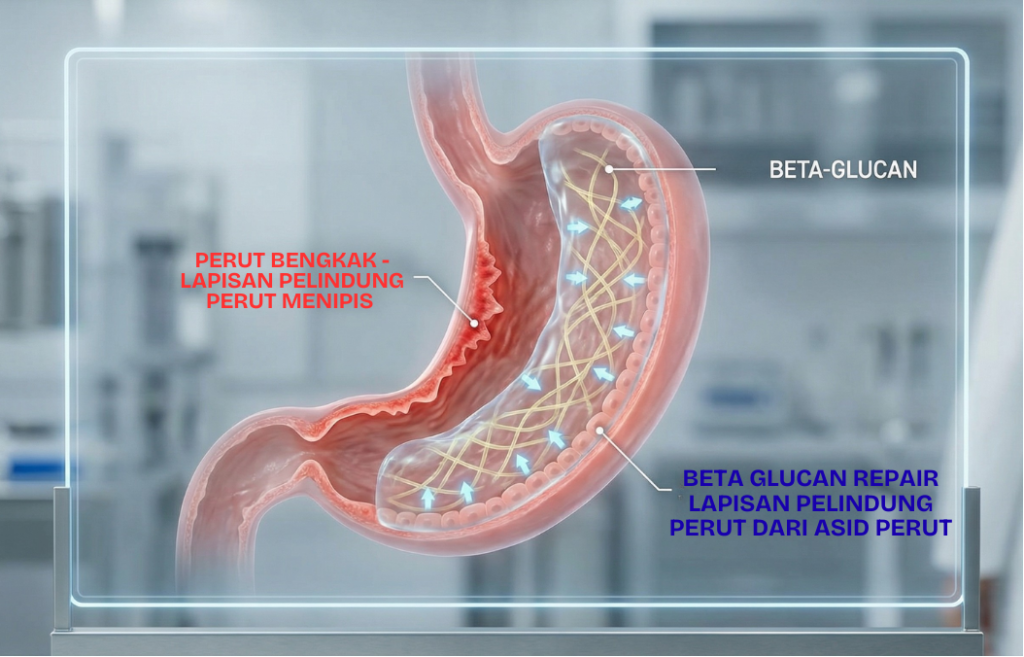

Lapisan pelindung perut yang menipis menyebabkan keradangan pada dinding perut akibat tindakblasa dengan asid perut.

FORMULASI SUSU KAMBING AJWA TALBINAH DIPERKAYA DENGAN BETA GLUCAN BERKESAN MEREDAKAN KERADANGAN DAN MEMBANTU MERAWAT LAPISAN PELINDUNG PERUT.

Ini ialah dinding perut menipis dan membengkak akibat lapisan pelindung menipis dan tidak dapat melindungi dari asid perut.

ini gambaran perut yang sihat dengan perut yang tidak normal

Barli beta glucan dalam Ajwa Talbinah mempunyai kandungan beta glucan, iaitu sejenis serat larut yang membantu memulihkan kesihatan perut & usus.

Lapisan pelindung perut yang sihat akan melindungi perut dari terkena asid perut yang kuat

Nota : asid perut diperlukan untuk penghadaman dan bunuh kuman dalam perut. Asid perut bukan masalah, tapi lapisan pelindung perut yang menipis itu masalah sebenar.